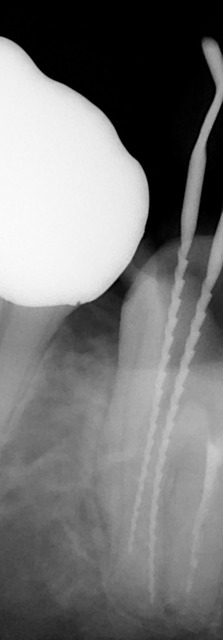

2根のところにリーマーを入れて、レントゲンを撮ったところです。

だいぶ根尖まで近づきました。

1根は根尖まで到達し(機械で計りました)

もう1根はもうちょっとで到達します。